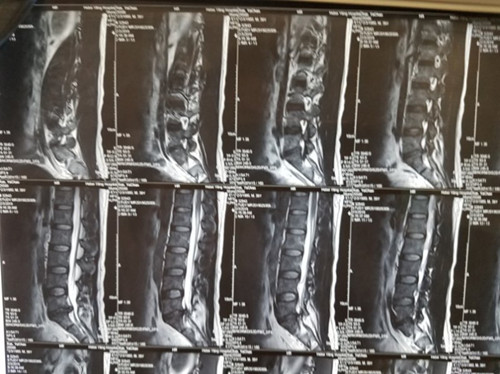

腰5骶1椎間盤(pán)突出